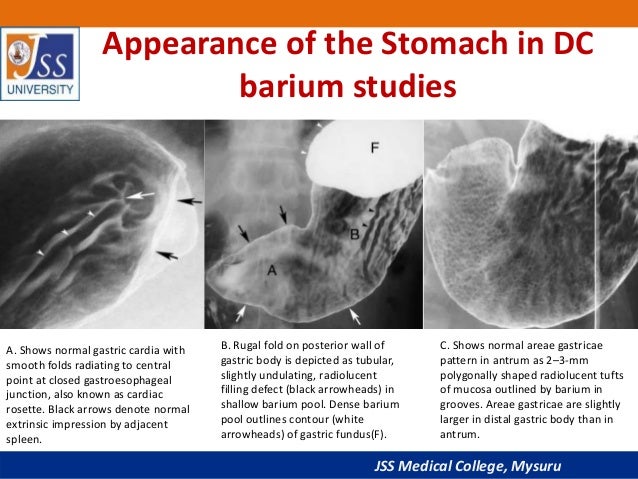

Gastric cardia radiology. Diagnostic centers of america dca is a leading diagnostic imaging facility offering a full array of imaging services in palm beach county florida. We have five state of the art radiology imaging centers in boca raton boynton beach delray beach and wellington florida. The gastric cardia is characterized on barium stud ies by three or four stellate folds that radiate to a central point at the gastro esophageal junction also known as the cardiac rosette fig 2 12. Variations and benign influences may closely resemble the more dangerous lesion.